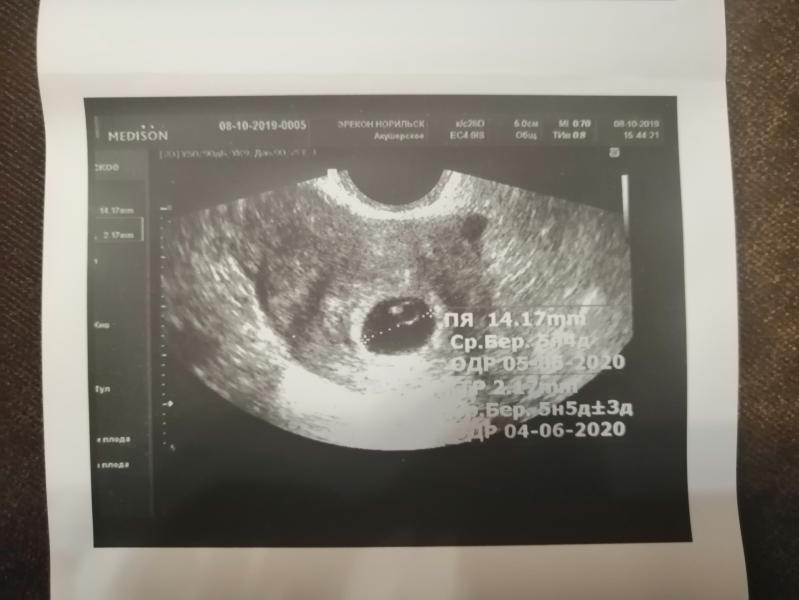

Чудо, произошедшее со мной!!! Но по порядку: 9,5 лет я замужем 2 раз. От 1 брака чудесная дочь, на днях ей исполнилось 14 лет! Второй муж все эти годы просил второго ребенка... А у меня то карьера, то квартира и тд... И вот в прошлом году дочь была месяц без меня в отпуске... Вот тут я завыла, я поняла, что скоро дочь улетит в другой город поступать, и мы останемся одни в большой квартире, с хорошей работой, но о ком так заботиться?! Вообщем, я решилась. В марте допила последнюю таблетку ОК. Цикл был от 15 до 57 дней... С мая по июль, я была в отпуске, вернулась 13.07 и приступили мы! Первый цикл пролет, 6 августа пришли месячные, в конце августа были покалывания в матке какие-то новые, сделать тест, пусто, хгч 1.2... 4.09. пошла на УЗИ, эндометрий очень тонкий, слабый фоликулярный аппарат, врач только качала головой, сказала надо лечить. 5.09 пришли месячные. 11.09 опять узи, эндометрий хороший, есть доминантный фоликул, врач (другая) сказала, через недельку будет овуляция. 20.09 по 24.09 пришли месячные... С 25.09 начала ловить овуляцию. Удивило, что все пять дней тесты были ну очень положительные. Мы с мужем очень старались! 3.10 приснился сон, что надо сделать тест на беременность. Сделала и... жирнючие // Побежала сдала хгч, почти 12000!!! Как??? Сегодня была на УЗИ! Уже бьется у моей бусинки сердечко 156 уд/мин! Это фантастика!!! Чудо! П. С. Дополню- у мужа ужасная СГ была, 11 % подвижных а+в, всего 34% живых, концентрация ниже нормы... Да и возраст у нас- мне 37, мужу 43. Вывод! Девочки, надо верить и надеяться на лучшее! У вас всех все получится!!! Только верьте!!! С Божей помощью 🙏

😊 скажите пожалуйста, 5 недель и 5 дней это акушерский срок или эмбриональный? и где делали ( если Норильск) спасибо😉